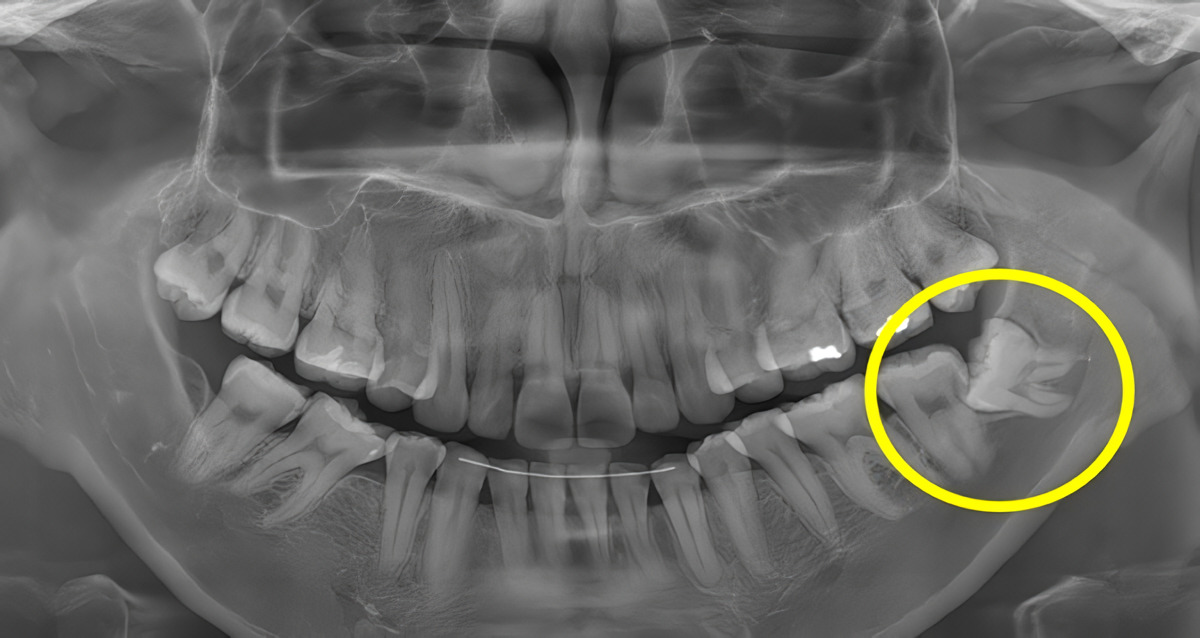

“μ¬λλ”λ μΉμ μ€ κ°μ₯ λ§μ§λ§μ λμ€λ μ΄κΈλλ‘, λ³΄ν΅ 17μΈμμ 25μΈ μ¬μ΄μ λλ μΉμλ₯Ό λ§νλ€. μμ΄λ‘λ “Wisdom Tooth”λΌκ³ λΆλ₯Έλ€.

“Wisdom Tooth”λΌλ ννμ μ¬λλκ° μΈμμ μ§νκ° μμ΄κΈ° μμνλ λμ΄μ λμ¨λ€λ μ΄μ λ‘ λΆμ¬μ§ μ΄λ¦μ΄λ€. μ΄ ννμμ “Wisdom”μ μ§νλ₯Ό μλ―Ένλ©°, λμ΄μ ν¨κ» μ»λ μ±μν¨κ³Ό κ΄λ ¨λμ΄ μλ€.